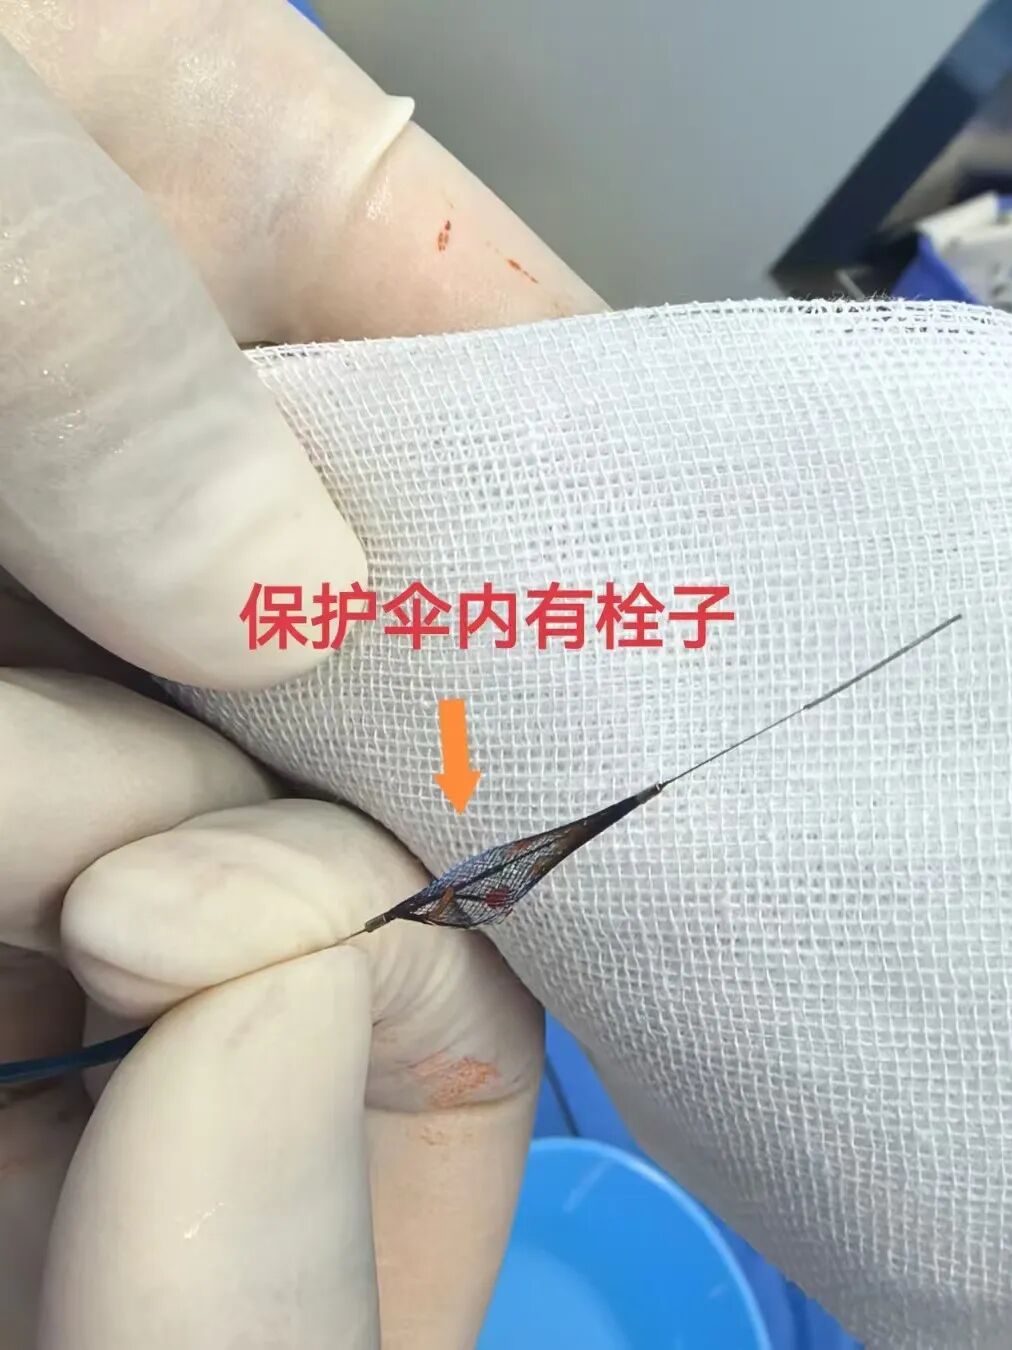

患者颈动脉保护伞中拦截栓子情况

为罗先生主刀脑血管部分手术的王和平教授介绍:“罗先生病情的最大险点就是颈动脉狭窄,是导致脑卒中的重要元凶。颈动脉支架植入术较传统手术创伤显著减小,但须严密管控斑块脱落风险。本次治疗通过术前三维影像学评估、术中脑保护装置精准应用及术后个体化用药方案与密切监测,构建了全流程精准医疗体系。”